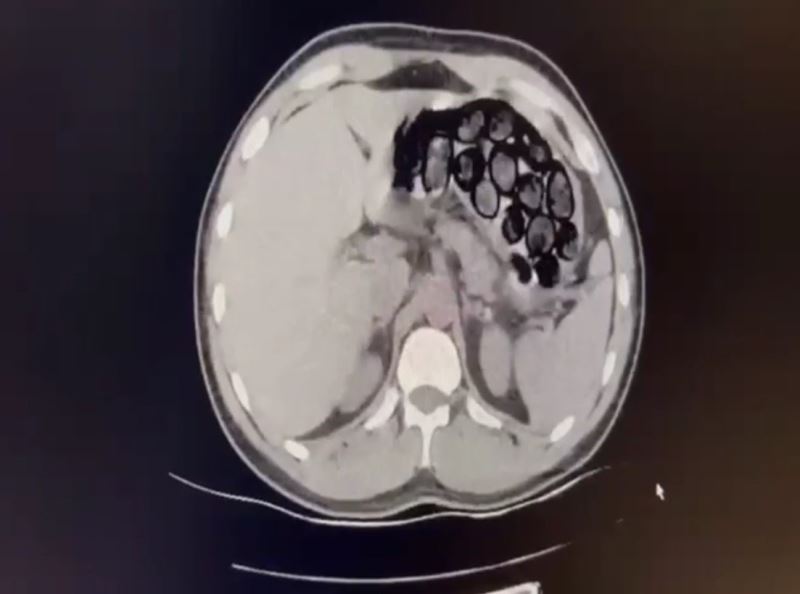

Jandarma ekiplerince takibe alınan İranlı şahıs ve beraberindeki 2 kişi, Kars’ın Selim ilçesi girişinde ticari takside yakalandı. Yapılan üst aramasında bir şey bulunamayan Omid Baghernezad, Kars Harakani Devlet Hastanesi’ne götürüldü. Burada çekilen röntgende Omid Baghernezad’ın mide ve bağırsağında kapsüller halinde 65 parça halinde 412 gram sentetik uyuşturucu olduğu belirlendi.